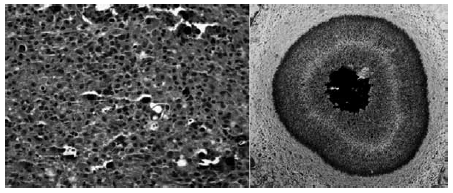

Nas doenças tubulointersticiais apresentadas na figura a seguir, na ME (microscopia eletrônica) o corpúsculo de Michaelis-Gutman é característico da seguinte patologia: